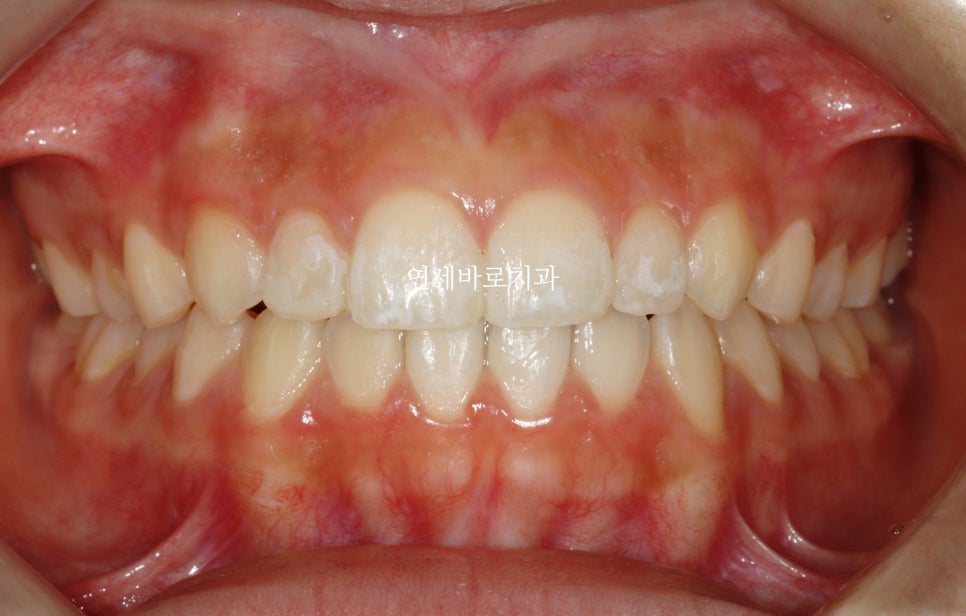

최종적으로 아이는 레진으로 임시로 공간을 매꾸기로 했습니다.

임시라지만 오랜시간 사용해도 됩니다.

이 문제를 해결하기 위해서는 무삭제라미네이트를 추천합니다.

하지만 당연히 저도 지금은 추천안해요

이유는 나이가 아직 어리기 때문입니다.

나이가 어리면 아직 잇몸의 성장이 남아있고, 그래서 지금 하면 나중에 성인이 되어서 경계부분이 맞지 않게 됩니다.

그래서 20세정도까지는 임시로 채워넣거나. 그냥 벌어진상태로 지내야 합니다.